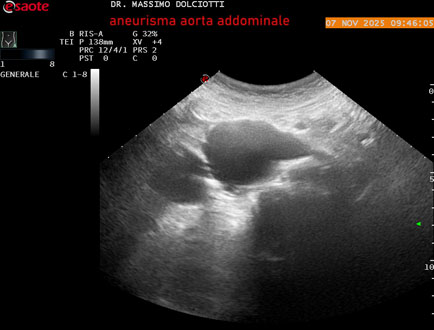

Data inserimento: 11/11/2025

Ecografia del: 07/11/2025

Strumento: Esaote MyLab Eight

Sonda: Convex Multifrequenza 1-8 MHz

Età Paziente: M 60 anni

Motivazione dell'esame: follow up per aneurisma dell'aorta addominale.

Commento all'esame: le immagini ed il video documentano la presenza dell'aneurisma dell'aorta addominale sotto-renale, con diametro antero-posteriore massimo documentato di 47 / 48 mm.

Conclusioni: aneurisma dell'aorta addominale in follow up (abdominal aortic aneurysm follow-up).

Presentazione: Dr. Massimo Dolciotti - Ancona